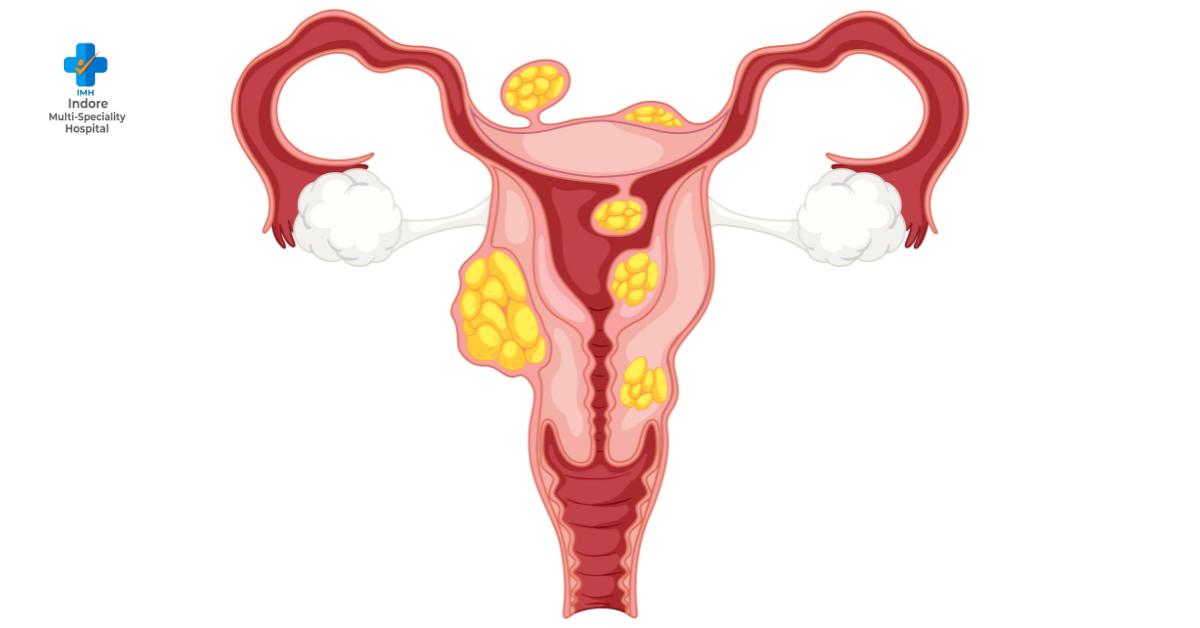

Polycystic Ovary Disease (PCOD) is a common hormonal disorder affecting young women, often leading to irregular periods, weight gain, and other health issues. Early detection and proper care are essential to manage symptoms and maintain long-term health. Seeking PCOD treatment in Indore at a reputed clinic can provide expert guidance and personalized care for women experiencing these challenges.

Recognizing PCOD in its initial stages can make a significant difference. Some early signs to watch for include:

Irregular Menstrual Cycles: Missing periods or having cycles that vary widely in length.